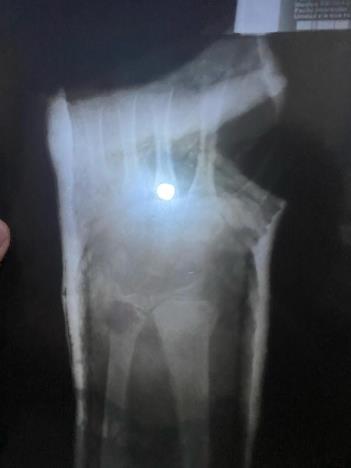

Graduarme de la prepa, romperme el brazo, conocer gente nueva, ingresar a la universidad, probar nuevos pasatiempos fue lo que más me marco.